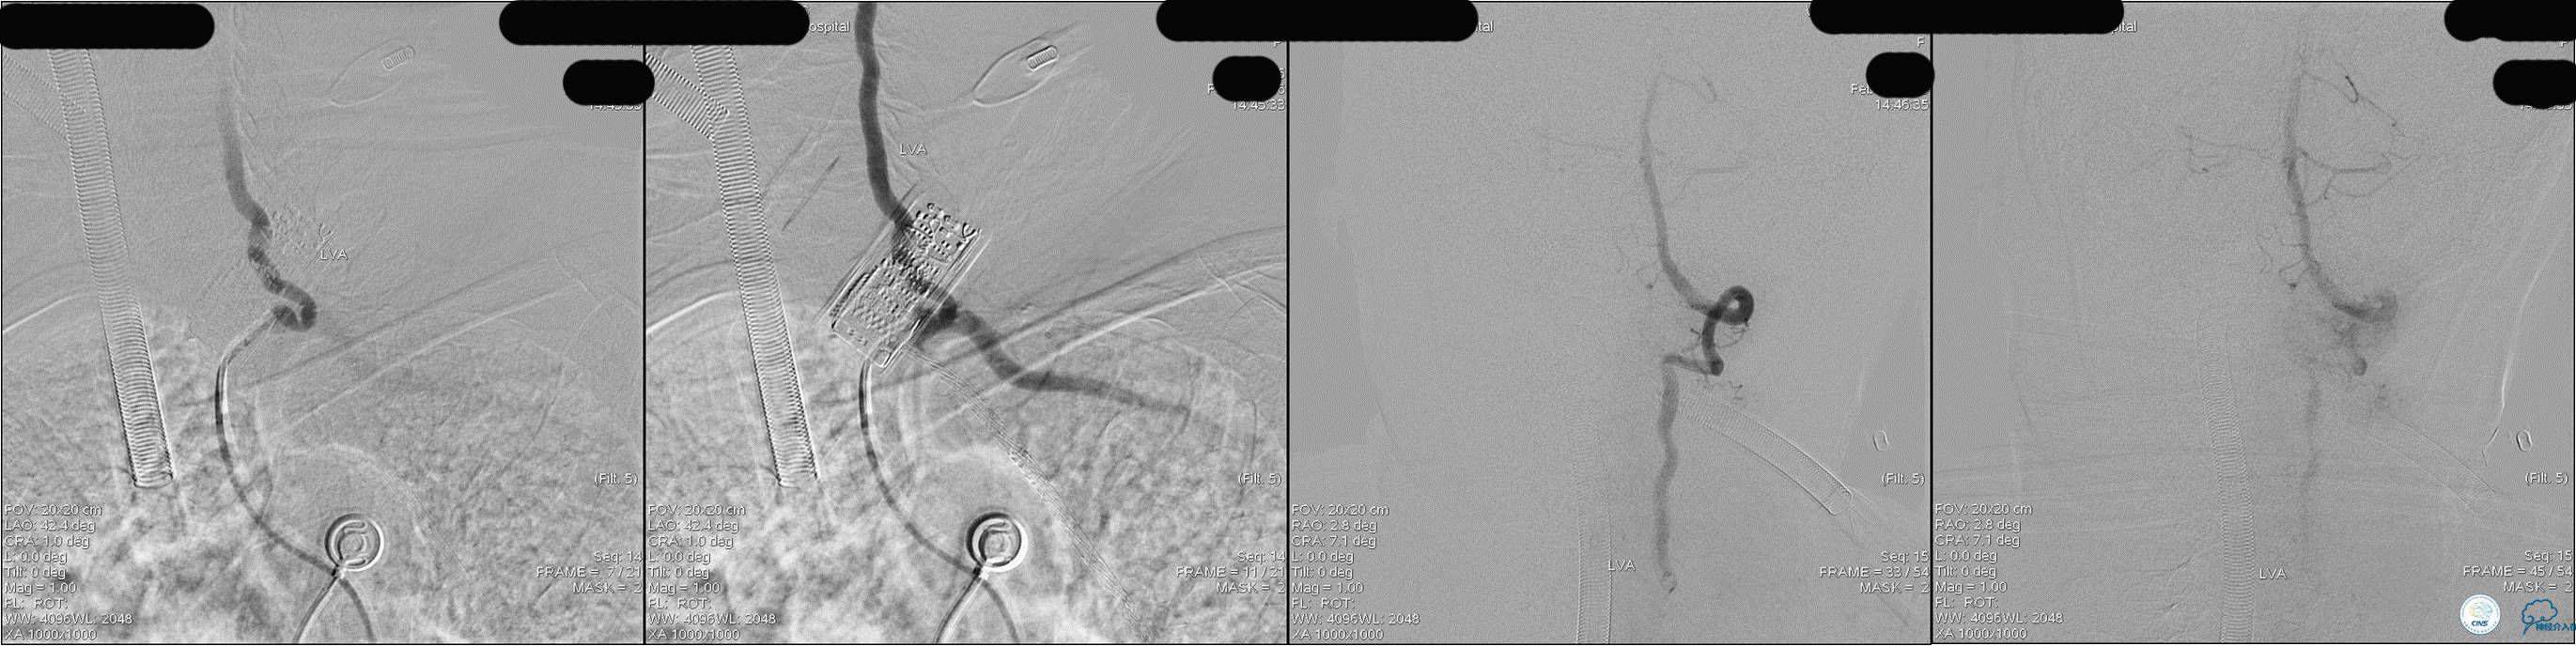

》DSA资料(经桡动脉,5F导引导管)

》DSA资料(右侧椎动脉)

》DSA资料(前2次取栓,未取出,soli 4-20)

》DSA资料(第3次取栓)

第3次取出血栓